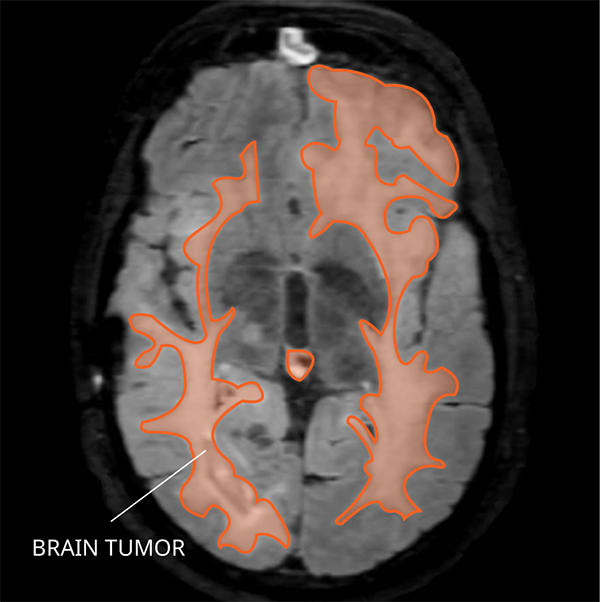

What Does Gliomatosis Cerebri Look like on an MRI?

Gliomatosis cerebri usually appears abnormal in three or more lobes of the brain on a magnetic resonance imaging (MRI) scan.

- Type 1 shows a widespread tumor pattern or a fluffy looking abnormality but no obvious mass.

- Type 2 shows a widespread fluffy looking tumor pattern, as well as a tumor mass.

Finding a gliomatosis cerebri on an MRI does not reliably predict the underlying tumor diagnosis based on tissue findings.